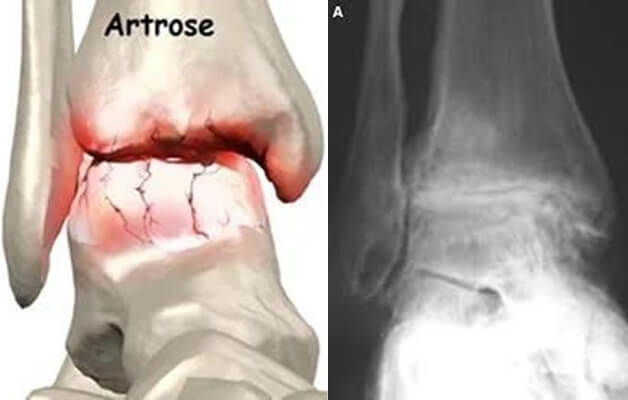

A osteoartrose do tornozelo é uma doença degenerativa que afeta a articulação do tornozelo. Leva ao desgaste progressivo da cartilagem, uma substância lisa e resistente que recobre as superfícies articulares e que permite o movimento suave da articulação, amortecendo o impacto e minimizando o atrito.

O diagnóstico por imagem é baseado em radiografias em carga, em que se visualiza o estreitamento do espaço articular, esclerose do osso subcondral, formação de osteófitos e possíveis deformidades articulares. A artrose do tornozelo pode passar despercebida nos estadios iniciais com as radiografias, podendo nestes casos ser necessário o estudo complementar com tomografia computorizada ou ressonância magnética.